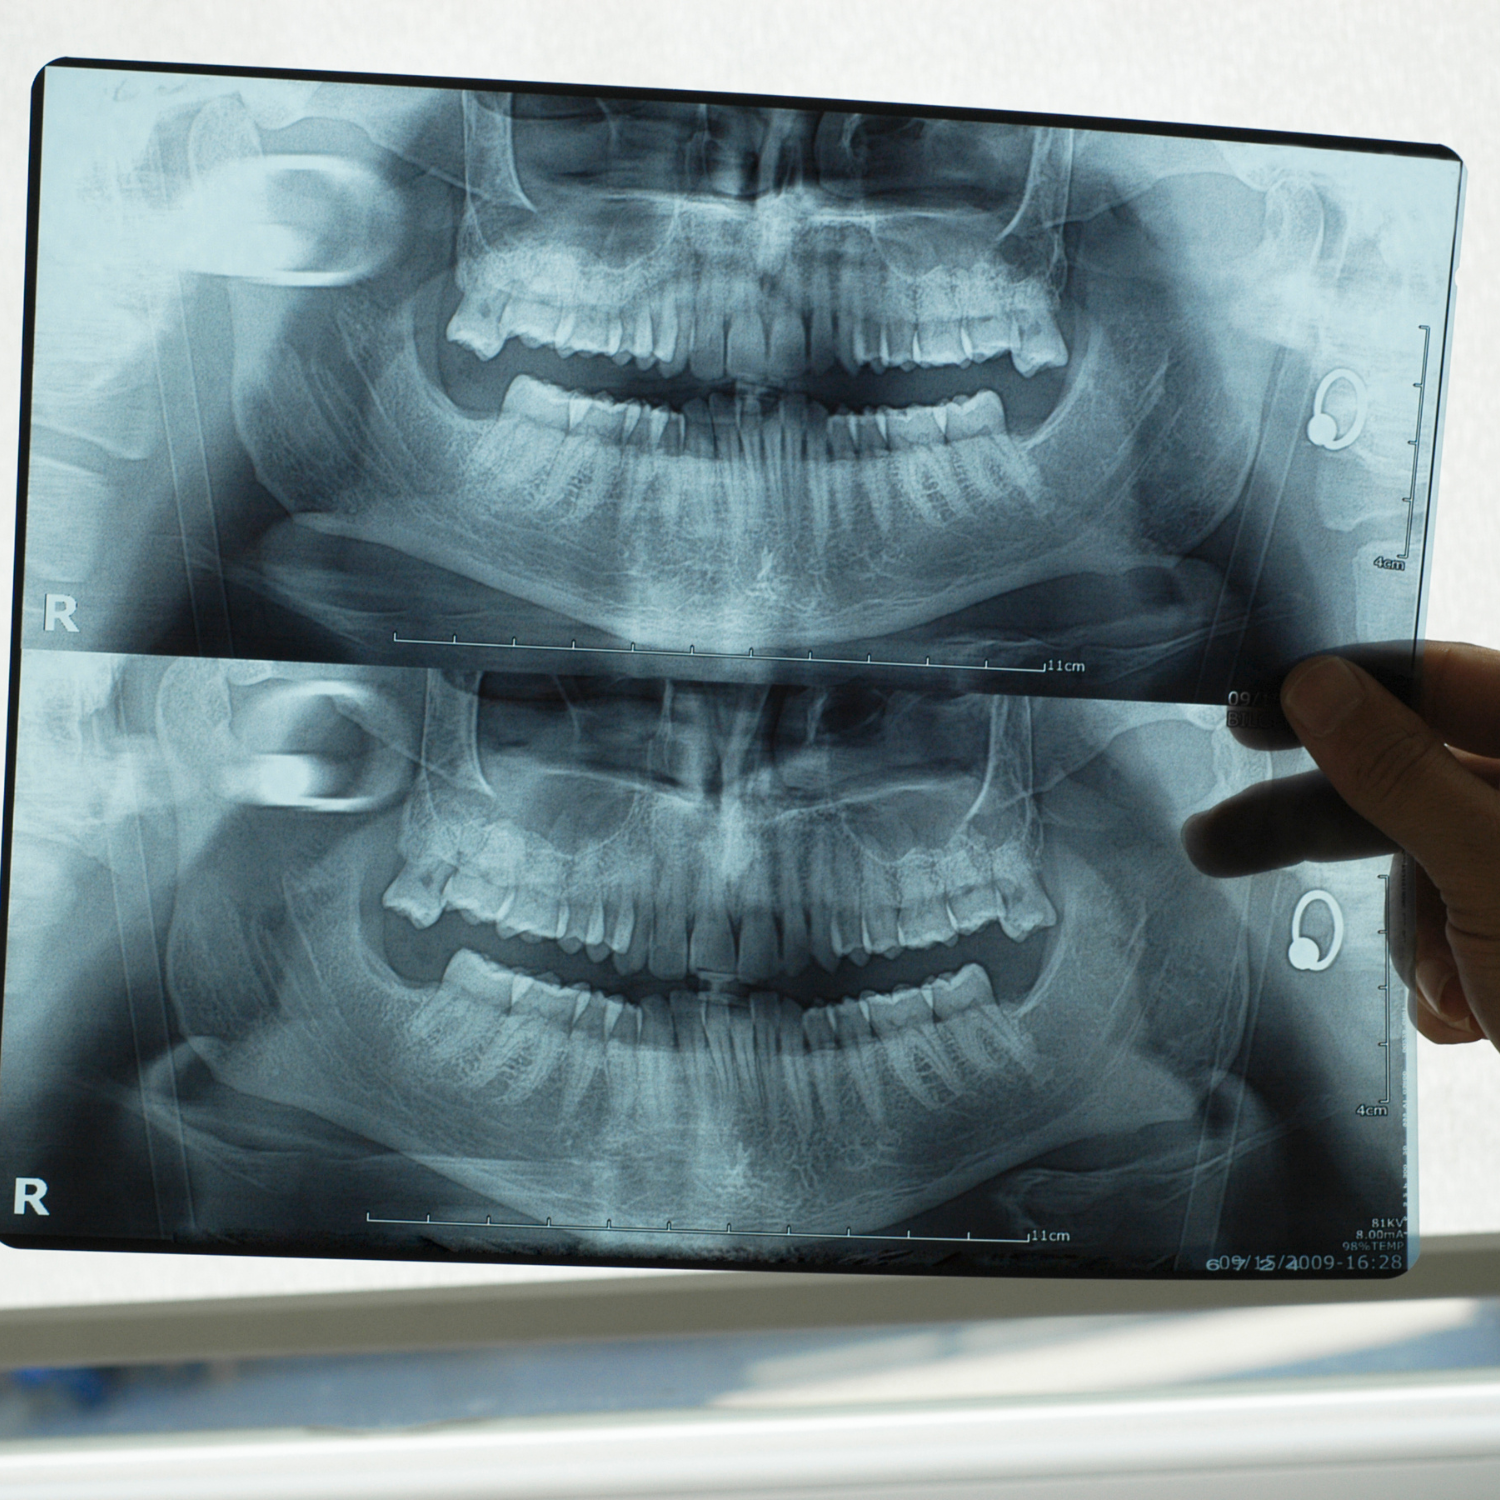

Radiographie (RVG)

La radiographie numérique RVG (Radiovisiographie) nous permet de réaliser des diagnostics précis grâce à des images claires et détaillées, tout en minimisant votre exposition aux rayonnements.